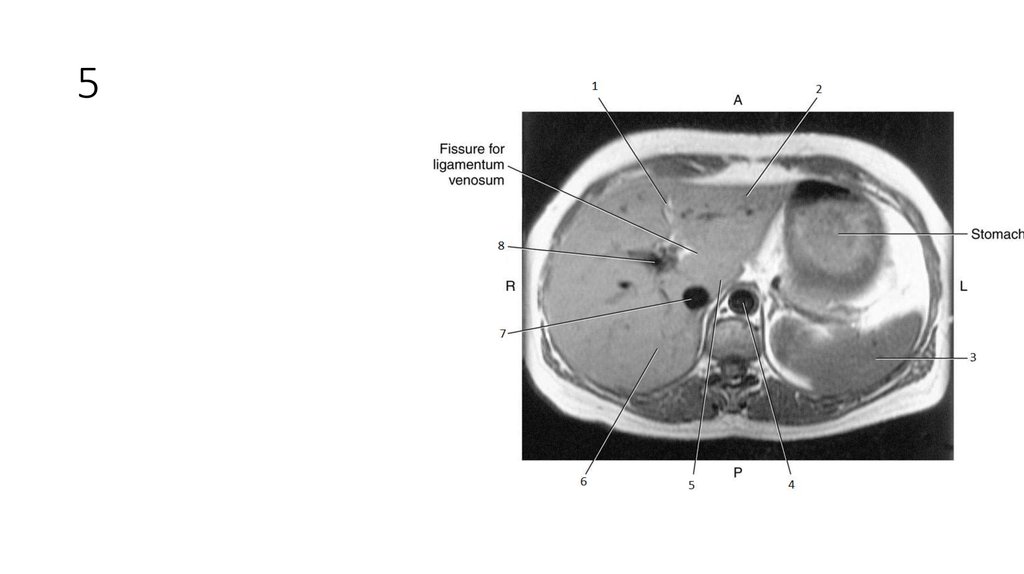

16. 1

• Falciform Ligament

17. 1

18. 2

• Left lobe of Liver

19. 2

20. 3

• Spleen

21. 3

22. 4

• Aorta

23. 4

24. 5

• Caudate Lobe of Liver

25. 5

26. 6

• Right Lobe of Liver

27. 6

28. 7

• Inferior Vena Cava (IVC)

29. 7

30. 8

• Portal Vein

31. 8